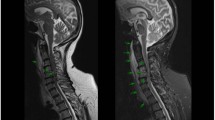

Cervical spinal fracture and pseudarthrosis are previously described causes of spinal cord injury (SCI) in patients with spondylarthropathy. SAPHO (Synovitis Acne Pustulosis Hyperostosis Osteitis) syndrome is a recently recognized rheumatic condition characterized by hyperostosis and arthro-osteitis of the upper anterior chest wall, spinal involvement similar to spondylarthropathies and skin manifestations including palmoplantar pustulosis and pustular psoriasis. We report the first case of SAPHO syndrome disclosed by SCI related to cervical spine ankylosis.